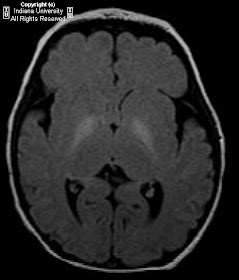

Findings

Increased signal intensity on T1 and FLAIR sequences in the bilateral globi pallidi and hippocampi.

Diagnosis: Kernicterus

MR imaging findings in the acute phase include increased T1 signal intensity in the globus pallidus, hippocampus, substantia nigra, and dentate nucleus. T2 signal may be subtly increased.

MR imaging findings in the chronic phase include increased T2 signal in the posteromedial border of the globus pallidus, hippocampi, and occasionally the dentate nucleus. T1 weighted images are normal.